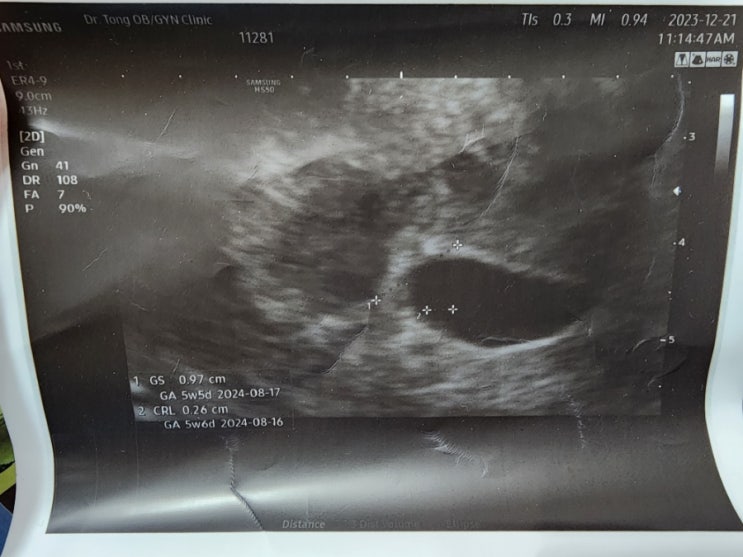

어쩌다보니..? 임신을

가을부터 임신을 준비해야지 하고는 있었는데, 막 엄청 열심히 준비한 건 아니고 되면 좋고~라는 마음으로 ...